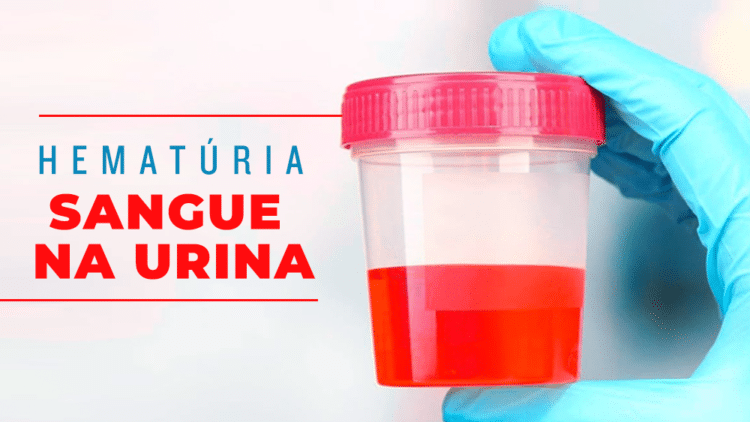

⚠️ Sintomas que Exigem Atenção

O sintoma mais comum e um sinal de alerta fundamental é a presença de sangue visível na urina (hematúria), que afeta cerca de 80% dos pacientes.